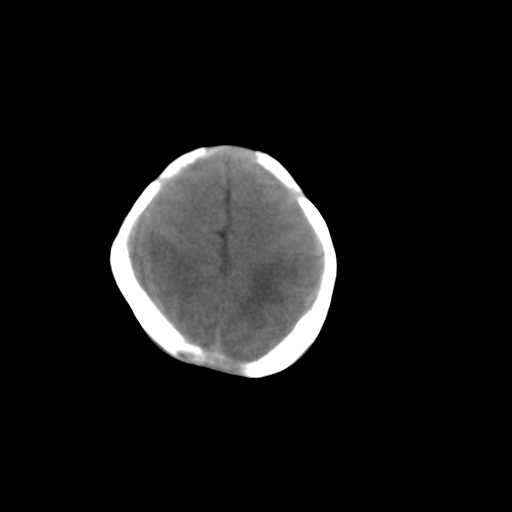

标题: PED1017:女,3天,足月顺产,出生后精神反应弱2小时。

女,3天,足月顺产,出生后精神反应弱2小时。

应该是大枕大池

依据:

1、低密度影由中线向两侧小脑表面延伸达岩锥

2、无明显占位效应

1)考虑hie。2)枕部颅骨内板下方类似囊状脑脊液样低密度影,鉴别于蛛网膜囊肿与巨大枕大池之间。